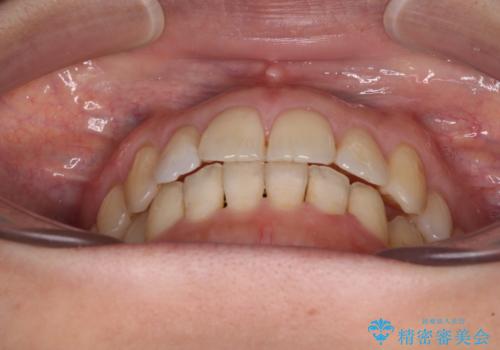

- 上下奥歯の欠損を気にして来院された患者様です。

以前矯正した後戻りにより前歯に叢生が認められたため、矯正治療の提案をしたところ、補綴治療と合わせて矯正治療を行うこととしました。

後戻りの程度は軽度であったため、インビザライン・ライトを用いて歯列を整えました。

再度後戻りするリスクを最小限に食い止めるため、下顎前歯の舌側を細いワイヤーで固定しました。